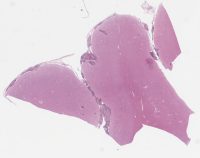

AANP2006-1.svs

64964 x 39065

@ 20X